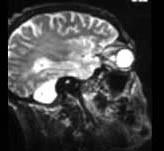

根据图示考虑是何种疾病 ( )A、小脑发育不良B、无脑畸形C、扁平颅底D、Arnold-Chiari畸形E、小脑扁桃体肿瘤

问题 根据图示考虑是何种疾病 ( )

选项 A、小脑发育不良 B、无脑畸形 C、扁平颅底 D、Arnold-Chiari畸形 E、小脑扁桃体肿瘤

答案 A